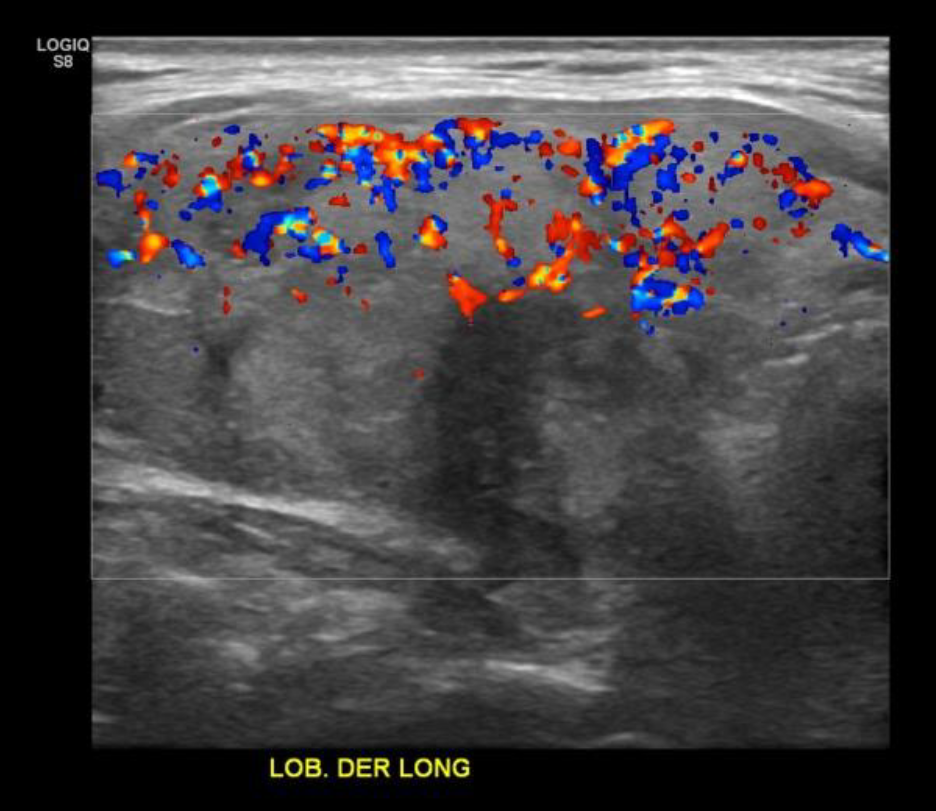

• Tiroides de parénquima heterogéneo, bordes irregulares, tamaño/vascularización conservada en LTI, no así LTD aumentado de tamaño/vascularización a expensas de los nódulos (3). → Bocio Multinodular

• LTD: N1: Nódulo sólido, hipo ecogénico, calcificación periférica (sombra acústica posterior), imágenes hiperecogénicas internas, señal periférica al DC.

• N3/N4: Nódulos sólidos, isoecogénicos, bordes definidos, señal periférica/interna al Doppler Color.

• En la Reg Cerv Der GIII se visualiza imagen de aspecto nodular sólida de gran tamaño, heterogénea con pequeñas imágenes hiperecogénicas puntiformes internas, bordes parcialmente definidos con señal interna/periférica al Doppler Color. Se visualizan imágenes de similares aspectos en Reg Cerv Izq GIII y GV. Signos sugerentes de extensión extra tiroidea de probable nódulo de aspecto maligno en LTD.

Presenta eco estructura interna heterogénea sin alteraciones del flujo vascular al estudio con Doppler-Color.

En el lóbulo tiroideo derecho lesión nodular ecogénica de 19 x 18 mm diámetro calcificada con sombra acústica posterior. Otra lesión nodular hipo ecogénica heterogénea en el polo inferior lóbulo derecho de 16 x 10 x 20 mm y otra de 11 x 11 x 10 mm, esta última con focos ecogénicos puntiformes sugerentes de calcificaciones. Adyacente al lóbulo derecho, lesión nodular hipo ecogénica heterogénea, de 27 x 60 x 23 mm, con focos ecogénicos sugerentes de calcificaciones. Glándulas submandibulares y parótidas de morfología normal. Linfonodos inespecífico en el grupo uno de 6 x 4 mm.